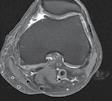

CT-ul cu reconstrucție tridimensională sau RMN genunchi relevă mult mai

bine complexitatea fracturii și dau posibilitatea unui planning preoperator superior estimării radiologice clasice(7). CT-ul este mai rapid și mai ușor de făcut, dar RMN decelează mai bine leziunile de menisc sau ligamentare.

Schatzker III, Osteosinteză cu șuruburi percutană

Schatzker VI, Reducere sângerândă și osteosinteză cu 2 plăci

fracturilor cu separare sau înfundare a platourilor tibiale, precum și a leziunilor de părți moi asociate ligamentare sau de menisc.

Se practică radiografii standard, examinare CT sau RMN.

Radiografiile se fac în cel puțin 3 incidențe: antero-posterioară, laterală și notch intercondilar.

Incidența antero-posterioară poate decela: o bandă osteoscerotică intensificată, specifică fracturii cu înfundare, separarea unui fragment osos, incongruență articulară femuro-tibială. O înfundare mai mare de 6 mm sau/și o incongruență articulară cu lărgirea acesteia mai mult de 5 mm sunt sugestive pentru leziuni de menisc lateral, ligament colateral lateral sau ligament încrucișat posterior(5). O înfundare sau lărgire articulară mai mare de 8 mm este deseori asociată cu o leziune de menisc medial(6).

Incidența laterală decelează traiecte de fractură postero-mediale.

În baza examenului radiologic au fost propuse mai multe clasificări, dar cea mai folosită este cea a lui Schatzker:

Schatzker I: fracturi cu separare hemiplatou extern

Schatzker II: fracturi cu separare și înfundare hemiplatou extern

Schatzker III: fracturi cu înfundare hemiplatou extern

Schatzker IV: fracturi hemiplatou intern

Schatzker V: fracturi hemiplatou extern și intern

Schatzker VI: fracturi cu extensie metafizo-diafizară

Totuși, 10% din fracturile de platou tibial nu pot fi încadrate în clasificarea Schatzker.